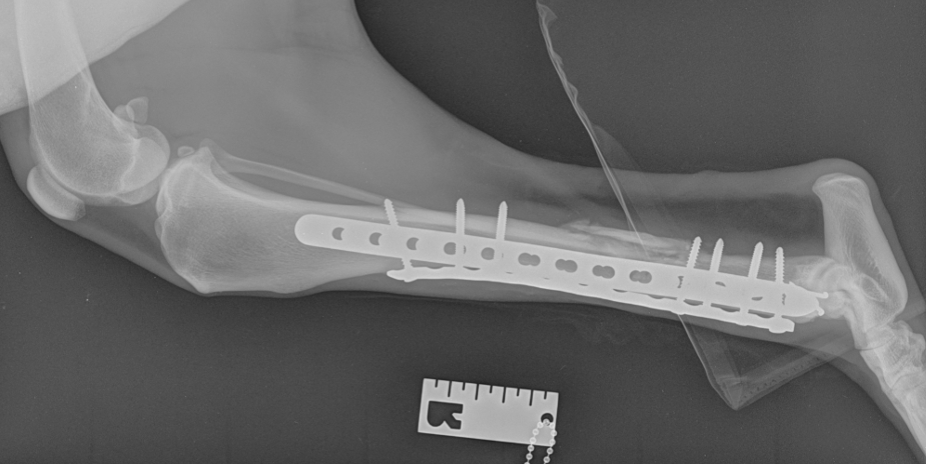

Fracture repair

Our fracture repair services

Locking plates.

AO/ASIF technique.

External fixator using IMEX.

Intramedullary locking nail.

Minimally invasive plate osteosynthesis (MIPO) with fluoroscopy